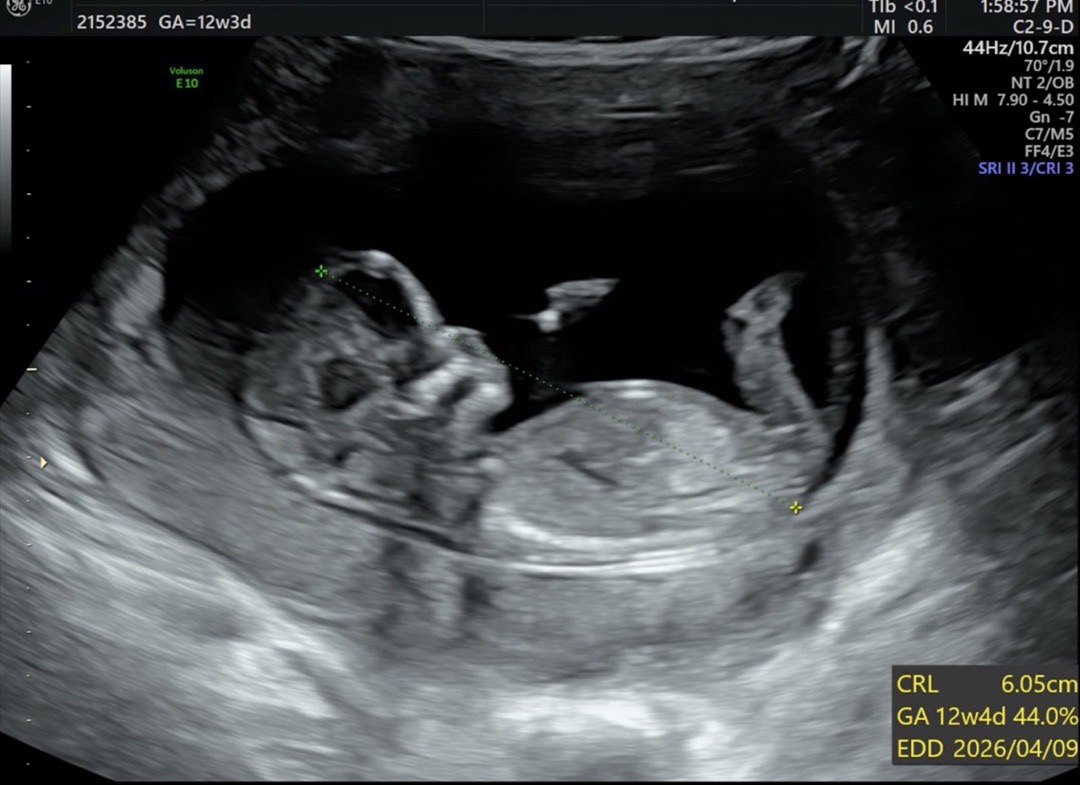

12주3일이에요!! 성별 같이봐주세요ㅜㅜㅜ

첫째가 아들이어서 딸을 간절히 원하고있는데ㅠㅠ 어떻게 보이시나요~~~ 마구 참견 해쥬세요 !